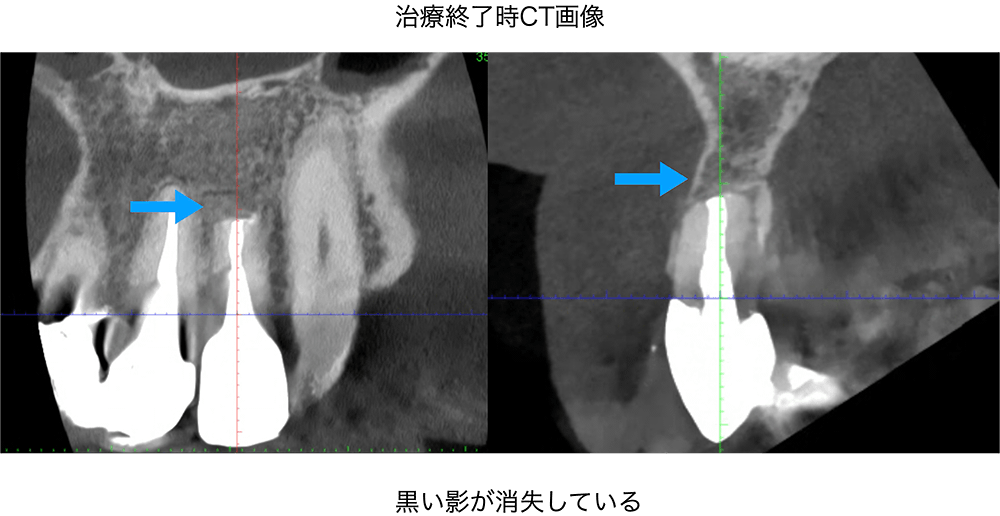

金山デンタルクリニックでは、治療の前に必ずCT撮影を行い、神経の本数や根の形、病変の大きさを正確に診査。治療の可能性や成功率まで含め、CTの画像を見せながら丁寧にご説明しています。治療後の経過もマイクロスコープやCT画像をお見せしながら、ご説明させていただきます。